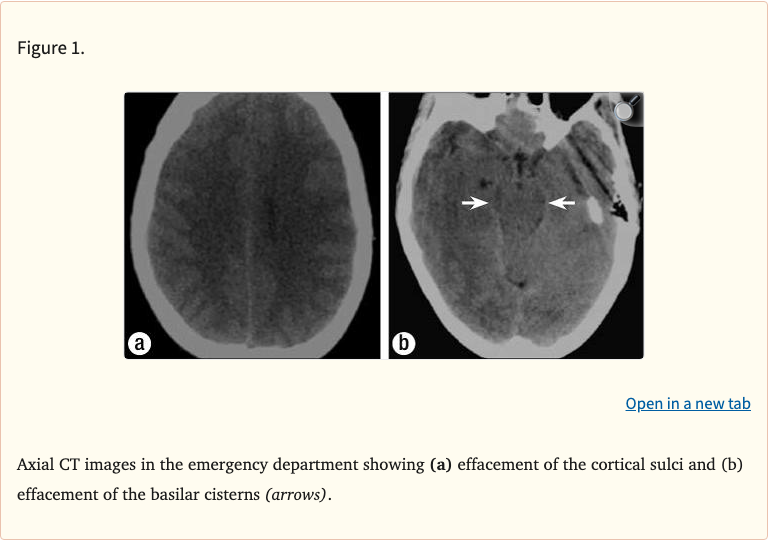

Figures